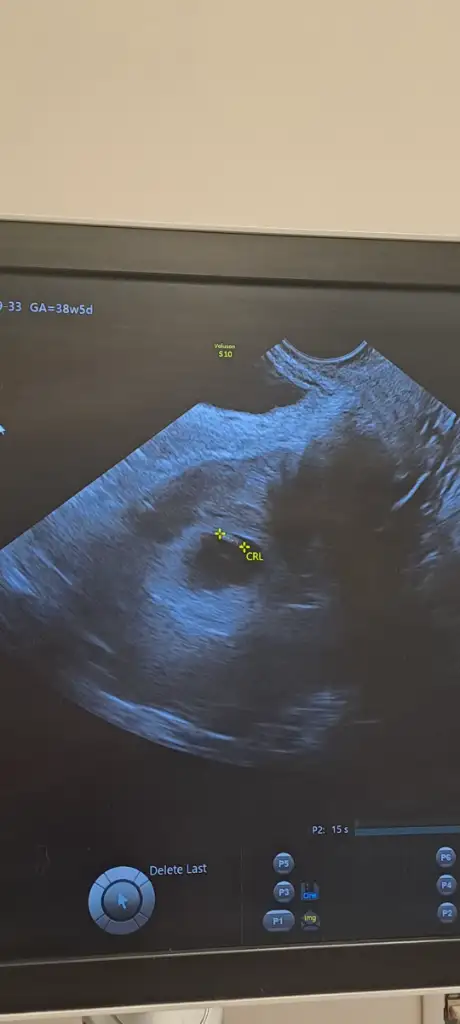

kızKızlar 12 haftalık gebeyim. Nub teorisine göre cinsiyet tahmini yapabilir misiniz? İlk bebeğimiz ve biz cinsiyeti çok merak ediyoruz![]()